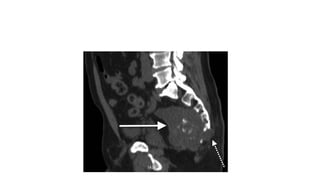

• 2)CT-Centrally located,well circumscribed, destructive lyric lesion with

sclerosis,expansile soft tissue mass

Investigations • 1)X-ray-Vertebral destruction •2)CT-Centrally located,well circumscribed, destructive lyric lesion with sclerosis,expansile soft tissue mass • 3)MRI-Low intensity T1 and high intensity T2